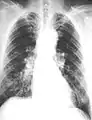

The abnormal chest x-ray and its interpretation remain the most important factors in establishing the presence of pulmonary fibrosis.[12] The findings usually appear as small, irregular parenchymal opacities, primarily in the lung bases. Using the ILO Classification system, "s", "t", and/or "u" opacities predominate. CT or high-resolution CT (HRCT) are more sensitive than plain radiography at detecting pulmonary fibrosis (as well as any underlying pleural changes). More than 50% of people affected with asbestosis develop plaques in the parietal pleura, the space between the chest wall and lungs. Once apparent, the radiographic findings in asbestosis may slowly progress or remain static, even in the absence of further asbestos exposure.[26] Rapid progression suggests an alternative diagnosis.

Extensive fibrosis of pleura and lung parenchyma.

Severe pleural fibrosis with focal calcification.

61 yr old working industrially with asbestos for decades.